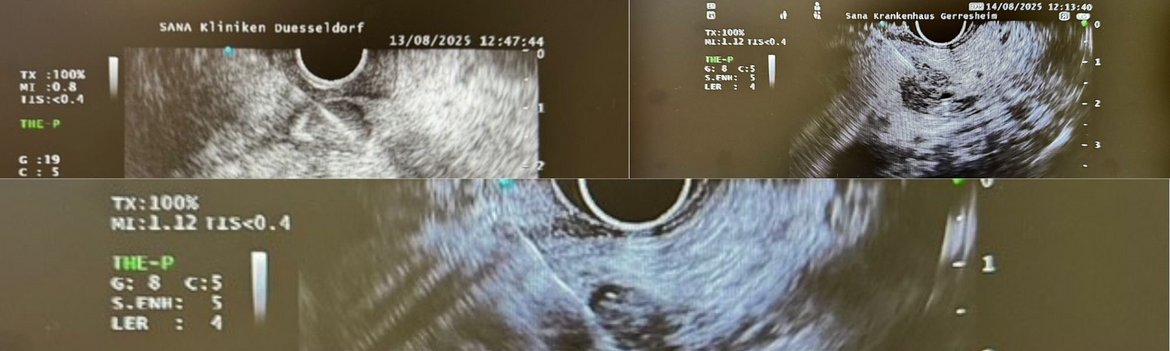

Endosonographie in der Diagnostik von Pankreaserkrankungen

In der Diagnostik und Therapie von Pankreaserkrankungen hat die Endosonographie (EUS) einen festen Stellenwert. Dabei werden zwei verschiedene Schallköpfe eingesetzt, die an der Spitze des Endoskops eingebaut sind. Der radiäre Schallkopf liefert analog zur Computertomographie ein 360° Bild, während der lineare Schallkopf, ähnlich wie ein Abdomenschallkopf, ein konvexes Bild und die Möglichkeit der ultraschallgesteuerten Punktion ergibt. Beide Schallköpfe haben die Möglichkeit einer Duplex-/ Kontrastmittelsonographie sowie Elastographie, so dass sicher zwischen Gang- und Gefäßstrukturen, als auch zwischen benignen und malignen Formationen unterschieden werden kann.

Der größte Vorteil der Endosonographie im Vergleich zur Computertomographie (CT) und Magnetresonanztomographie (MRT) liegt in der durch die Ortsnähe bedingten hohen Auflösung und durch die Möglichkeit beliebig wiederholbarer Schnitte, womit auch Läsionen im Millimeterbereich sicher erkannt und eingeschätzt werden können. Ferner sind hierdurch komplikationsarme Gewebeproben von suspekten Strukturen während des Untersuchungsvorganges möglich. Die in der Durchführung sehr anspruchsvolle Methode wird überwiegend in gastroenterologischen Zentren eingesetzt – auch am Sana Standort Gerresheim. In differentialdiagnostisch schwierigen Fällen ergänzen sich die Methoden EUS, CT und MRT.

Zusammengefasst handelt es sich bei der Endosonographie um ein risikoarmes, etabliertes, nicht durch Strahlung belastetes Verfahren in der Diagnostik von Pankreaserkrankungen, das bei vielen Patienten einen sehr hohen zusätzlichen Informationsgewinn ergibt. „Therapeutisch hat die EUS vor allem in der transgastralen oder trans-duodenalen Drainage von Sekretverhalten im Oberbauch eine etablierte Indikation. Auch in der Diagnostik und Surveillance der chronischen Pankreatitis und ihrer Komplikationen hat die EUS in der Hand des Experten einen hohen Stellwert und ist belastungsarm durchführbar“, so Dr. Michael Birkenfeld, Chefarzt des Viszeralmedizinischen Zentrums und spezielle Gastroenterologie an den Sana Kliniken Düsseldorf.